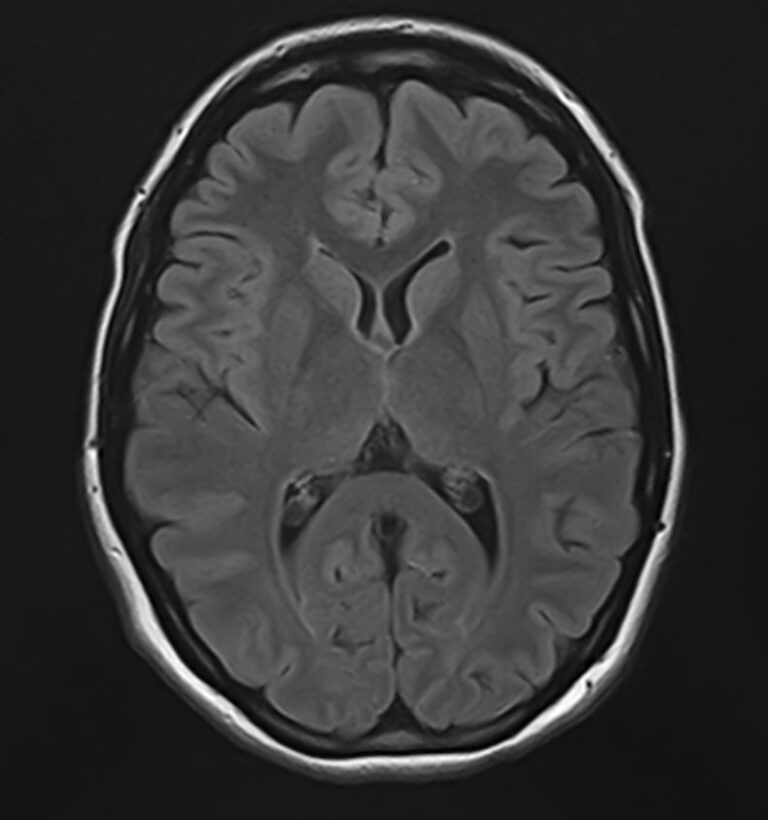

К центральной нервной системе организма относится головной мозг, расположенный в полости черепа, и спинной мозг, проходящий в спинномозговом канале позвоночного столба. В головном мозге находятся высшие центры управления всем организмом, спинной мозг имеет двусторонние связи с ними, то есть является проводником импульсов от периферии к головном мозгу и обратно.

Для диагностики заболеваний ЦНС в клинике «Доступная медицина» проводится комплексное обследование МРТ ЦНС (центральной нервной системы). Клиника укомплектована высокотехнологичным оборудованием, в частности, новейшим 32-канальным высокопольным томографом TOSHIBA VANTAGE TITAN 1,5 Тесла с высокой разрешающей способностью для точной диагностики заболеваний центральной нервной системы.

Комплексное обследование ЦНС выполняется как в стандартном режиме, когда не применяется использование контраста, так и с контрастным усилением. Для более точной диагностики некоторых патологий головного и спинного мозга внутривенно вводится контрастное вещество. С помощью контраста можно обнаружить опухолевые образования размером от 1 мм, демиелинизирующие процессы, дегенеративно-дистрофические заболевания, воспалительные процессы, сосудистую патологию.